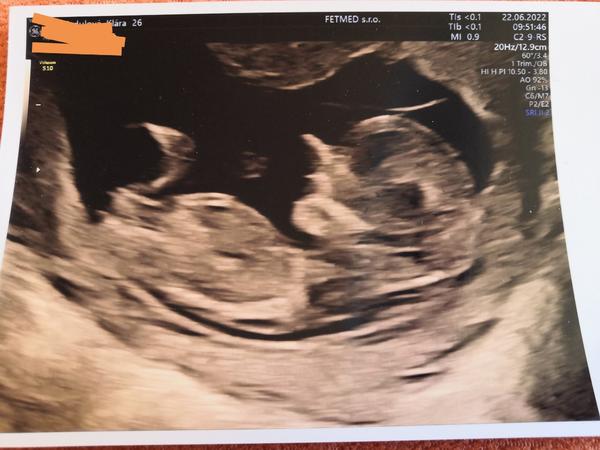

Pohlaví podle hrbolku. Tipl by si někdo?

Ahoj, je tady někdo, kdo by si tipl určit pohlaví podle hrbolku? Vím, že tady takové diskuze již jsou ale jsou staršího roku, takže jsem proto založila novou diskuzi. Snad to nebude vadit. Nejdůležitější je samozřejmě zdravé miminko, jen mě hlodá zvědavost, tím jak sedím doma a nemám do čeho píchnout. 🤷😁😁